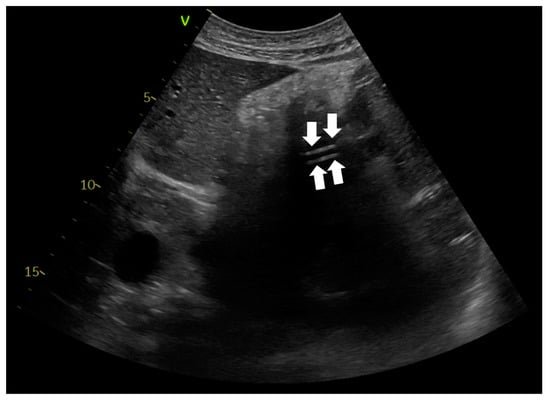

A nasogastric tube was placed in every patient with COVID-19 ARDS, upon ICU admission. Critical care physicians inserted the NGTs. Confirmation of correct NGT placement was performed with abdominal ultrasonography using a convex probe with low frequency (2–5 MHz). The probe was positioned in the sagittal and longitudinal epigastric section. Correct NGT placement was considered if either a single or double parallel lines of the tube were visualized in the gastric antrum or pylorus (Figure 1) and/or there was a dynamic appearance of air entering the stomach, instilled through the NGT (ultrasonographic whoosh test) (Videos S1 and S2). Confirmation was considered is cases in which both ultrasonographic tests were present or there was one ultrasonographic test and a positive “palpation test”. A positive “palpation test” was considered the test when a “flash” of air was palpated in the epigastrium, after installation of 50 mL of air through the NGT. When correct NGT placement could not be evaluated with one of the abovementioned criteria, an abdominal X-ray was ordered, and enteral nutrition was delayed until the radiograph was performed. Confirmation of correct NGT position was re-performed using ultrasonography every time the patients returned to the supine position after they had been proned, or whenever critical care physicians or nurses considered that reconfirmation was necessary.

Ultrasonographic evaluation of NGT position was performed in 276 patients, and confirmation of correct NGT placement was feasible in 246/276 (89.13%) patients. In 189/246 (76.8%) the tube could be visualized in the stomach (Figure 3), in 172/246 (69.9%) the ultrasonographic whoosh test was evident (Figure 4, Videos S1 and S2), while in 164/246 (66.7%) both tests confirmed correct NGT placement. All the patients had additional confirmation with palpation of a “flash” of air in the epigastrium instilled through the NGT. In the patients in whom the NGT could not be visualized and an ultrasonographic whoosh test was negative, a chest X-ray was performed. In all patients the NGT was located in the stomach.

Figure 2. Abdominal ultrasonography. Ultrasonographic confirmation of nasogastric tube presence in the stomach. The liver is seen on the left of the image. Two parallel lines are noted, corresponding to the NGT (white arrows).